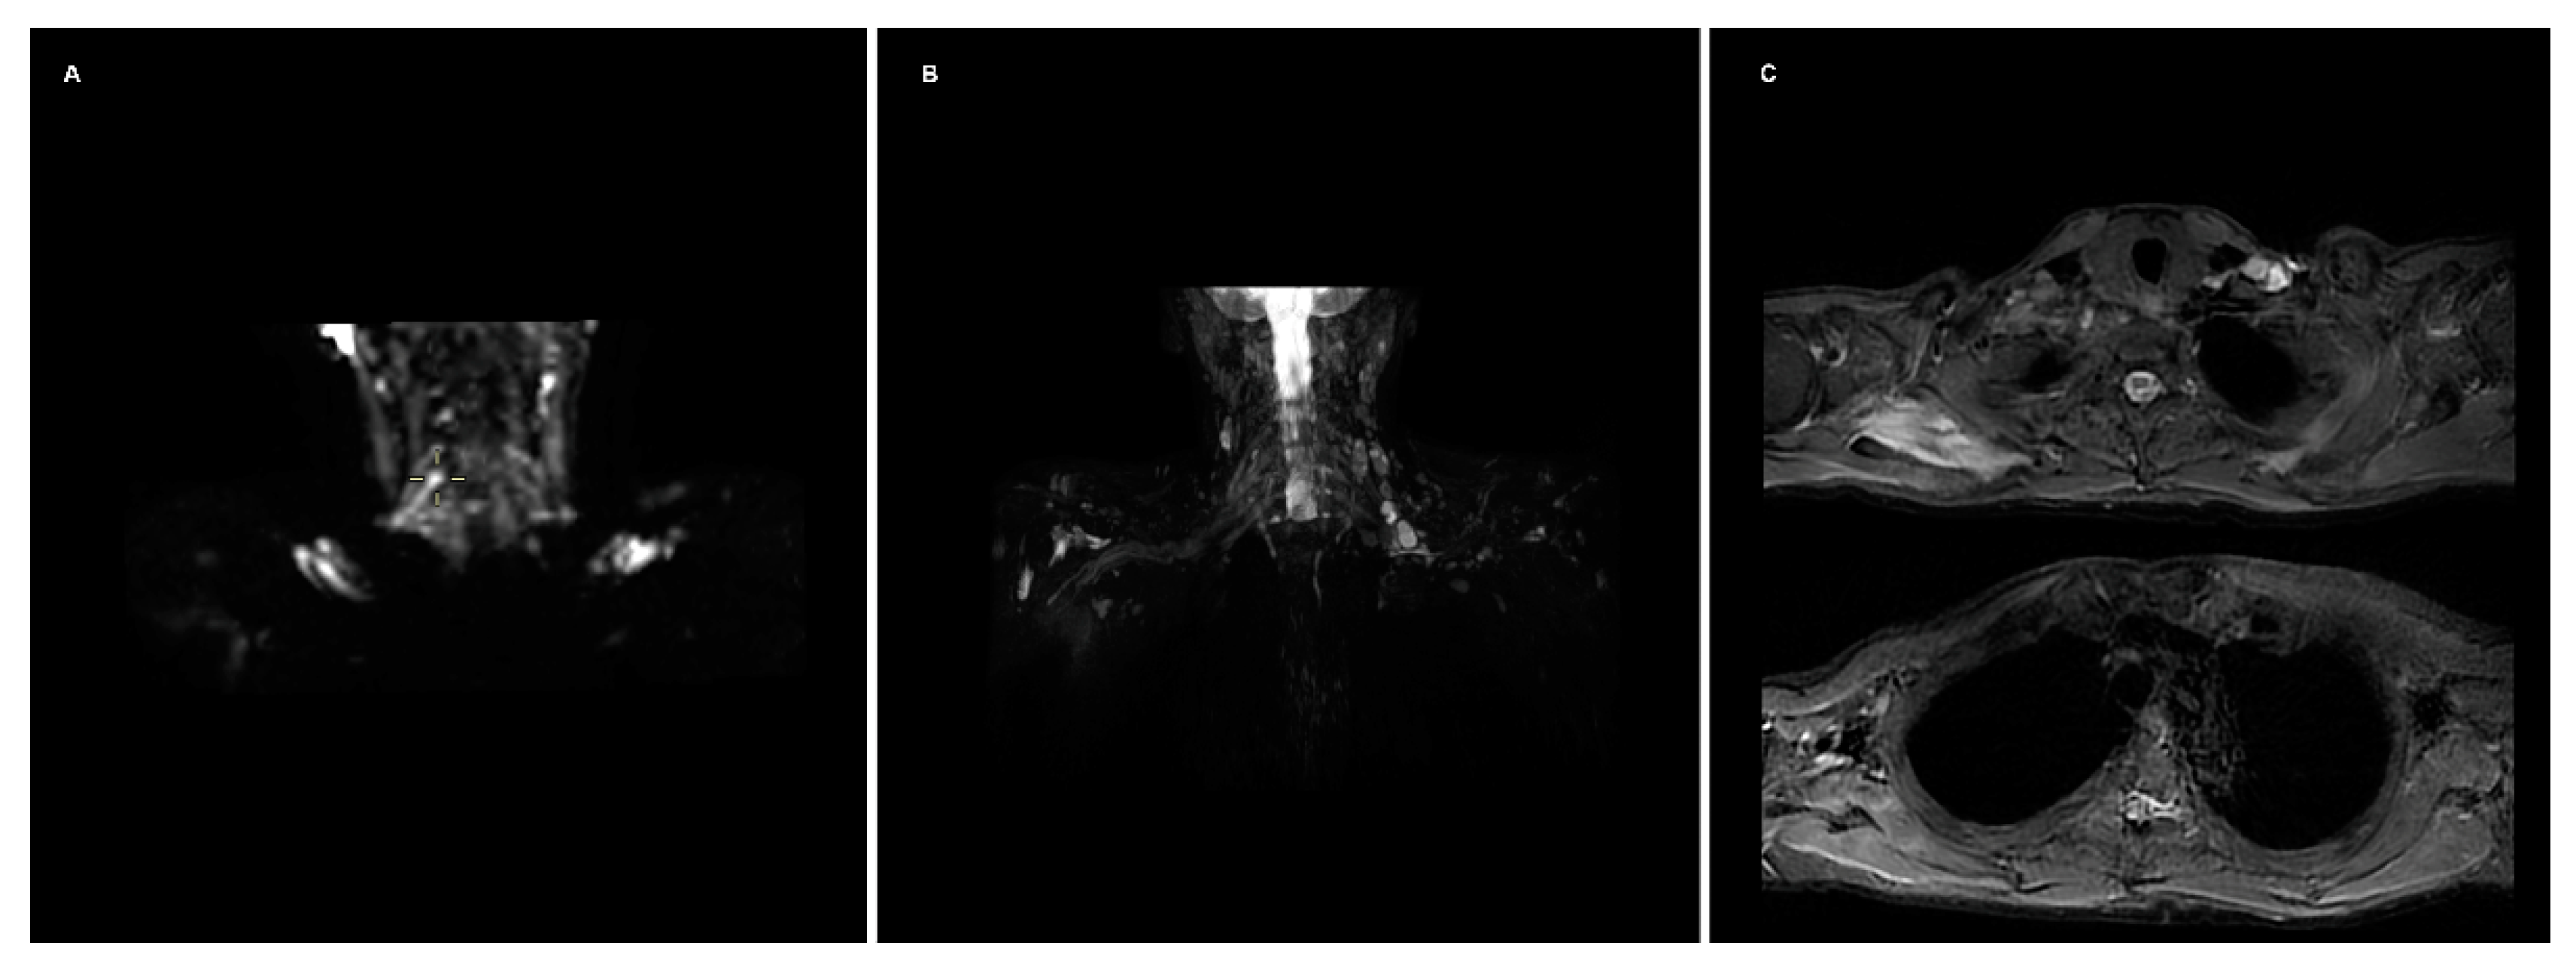

:- FIESTA: This steady-state sequence is not very susceptible to flow artifact, so it provides an excellent signal-to-background contrast for nerve roots and allows the detection of pseudomyelomeningoceles. Its fast acquisition time, <2 min, allows it to be incorporated in a standard acquisition protocol for the spine, or even implemented in emergency departments with an available MRI [1]. It has substituted the previous gold standard, the CT-myelography, which has the disadvantages of contrast media administration in the spinal canal and the use of ionizing radiations (particularly important in the obstetric lesions) [2].

- STIR: Nerves are isointense compared to muscle in T2-weighted sequences, and an hyperintensity can be a consequence of various pathological processes. The presence of a nodular formation on the course of the nerve is indicative of a neuroma, the detection of which MRI has shown a great accuracy of up to 99% [1,3]. The STIR sequence is often preferred over the T2 with fat suppression due to the homogenous fat saturation obtained. Moreover, the depiction of nerve fibers can be further enhanced with the administration of gadolinium, which suppresses the signal generated by the vessels improving the signal-to-background of the nerves [3]. This sequence also allows examining for muscular signal alteration, to properly stage the nerve injury [4].

- DWI/T2-weighted trace: DWI significatively improves the conspicuity of the nerves compared to T1- and T2-weighted sequences, and is the best alternative to DTI, over which it has the advantages of lower acquisition time and limited need of post-processing [5,6]. The most used b values are 600–700 (so that b × ADC = 1) [7]. A lower b-value with a reduced number of excitations can be added to the sequence, to calculate the ADC map, particularly useful in oncological patients. T2-weighted trace is the isotropic DWI resulting from the DTI post-processing, today a task often performed automatically by the machine’s console, so every study comprising a DTI sequence has isotropic DWI images available [8].